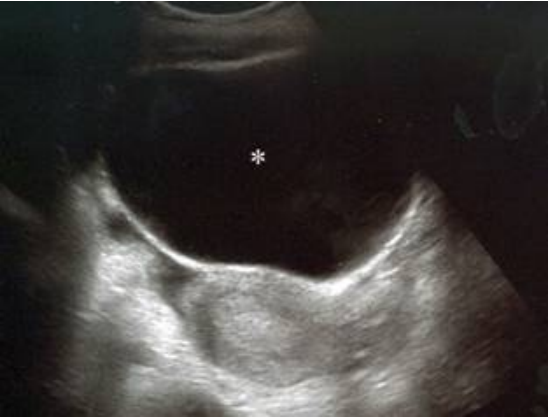

38 一位 16 歲智能不足且無性經驗之女孩,長期有慢性便秘之情形,近日因下腹脹痛及小腹微凸而到院 接受診察。經腹部超音波發現腹中有一水囊狀物(如下圖*處),位於子宮上面。子宮體之矢狀切面 大小為 5×4 公分,子宮內膜厚度為 1.4 公分,對此水囊狀物作進一步鑑別診斷之最適合處置為何?

(A)電腦斷層掃描或核磁共振造影檢查 (B)子宮內視鏡檢查及子宮內容物搔刮手術 (C)經腹部水囊穿刺囊液並送細胞學檢查 (D)導尿後再次超音波掃描